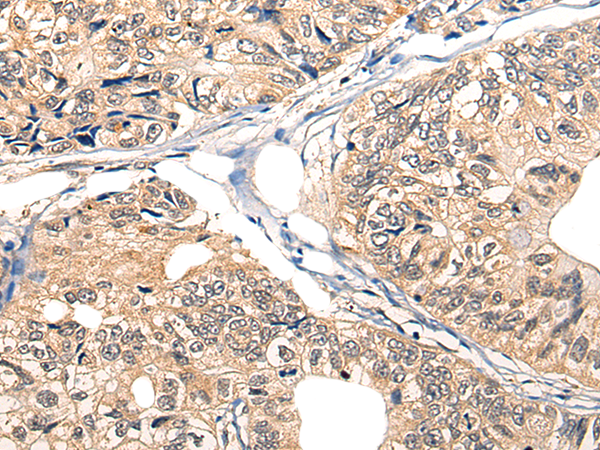

IHC positive control: |

Human liver cancer |

IHC Recommend dilution: |

25-100 |